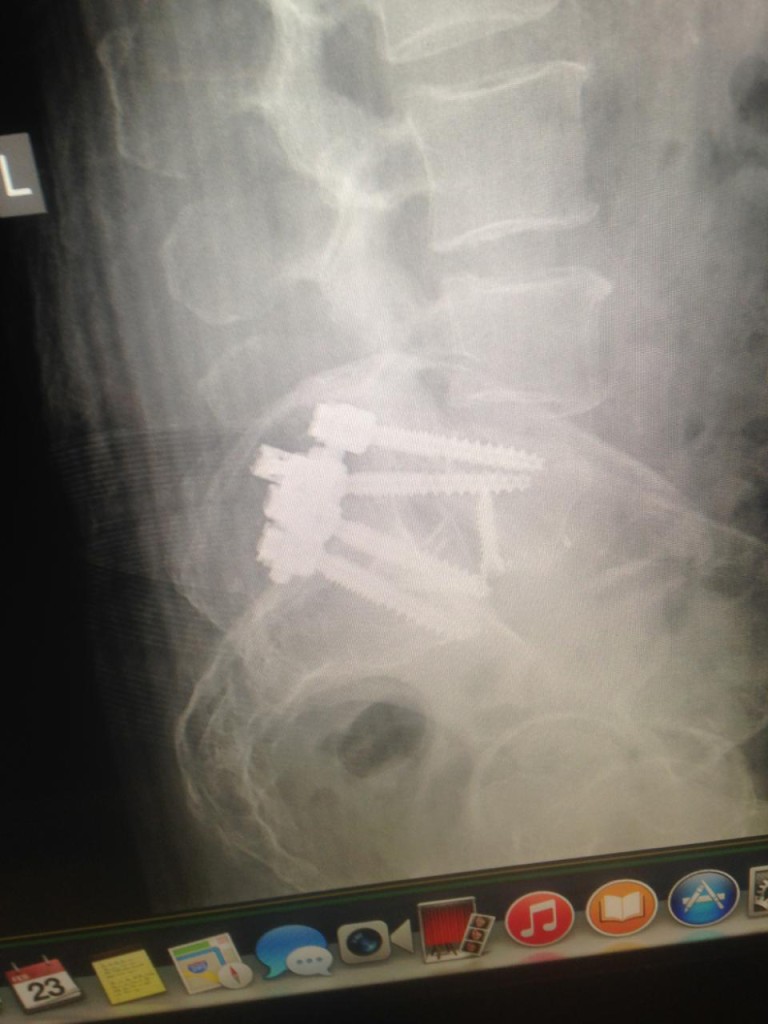

When I went to HSS for my surgery, I didn't know what to expect, but I think it was the best decision I ever made. I was in so much pain I could just about walk, I was told by Dr. Sama that he was going to anterior lumbar body fusion L5 S1 with posterior lumbar decompression, fusion, segmental spinal instrumentation L6 to S1 and I said "WOW! I don't have clue, but it takes away the pain and I can walk again lets do it." So January 12, 2015 was the date. My goal is to get back on the golf course play golf and to have many years of fun with my wife and family without PAIN. HSS has treated me with the care and respect that anyone going through what I have would need. It has been 7 weeks since my surgery and I am feeling better every day. The pain I had before the surgery is gone. I would just like to thank Dr. Sama and his staff for doing a great job. Also, all the people in the hospital, pain management, and any one that has helped when I had my surgery. I KNOW THAT WITH THE HELP OF HSS, I WILL BE BACK IN THE GAME ON THE GOLF COURSE. THANKS AGAIN.